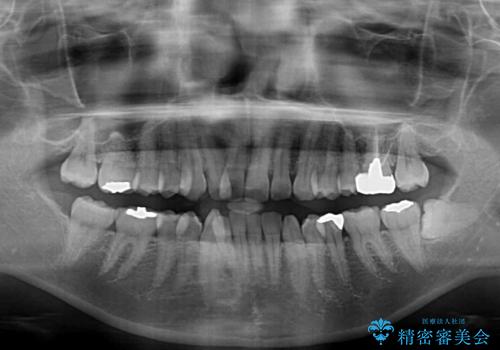

上下左右の第一小臼歯4本を抜歯して治療を行うことがセオリーでしたが、左下は第二小臼歯が銀歯であったため、イレギュラーではありますが、そちらを抜歯しました。

その影響で治療期間は長くなりましたが、処置していない歯を保存することができました。